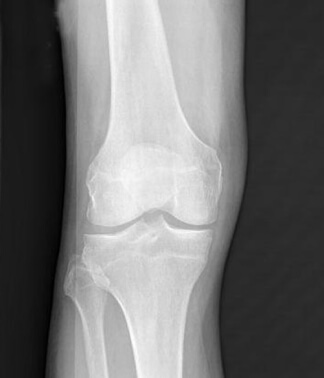

RTG desnog kolena Milane Topić. Hrskavično tkivo je gotovo potpuno uništeno.